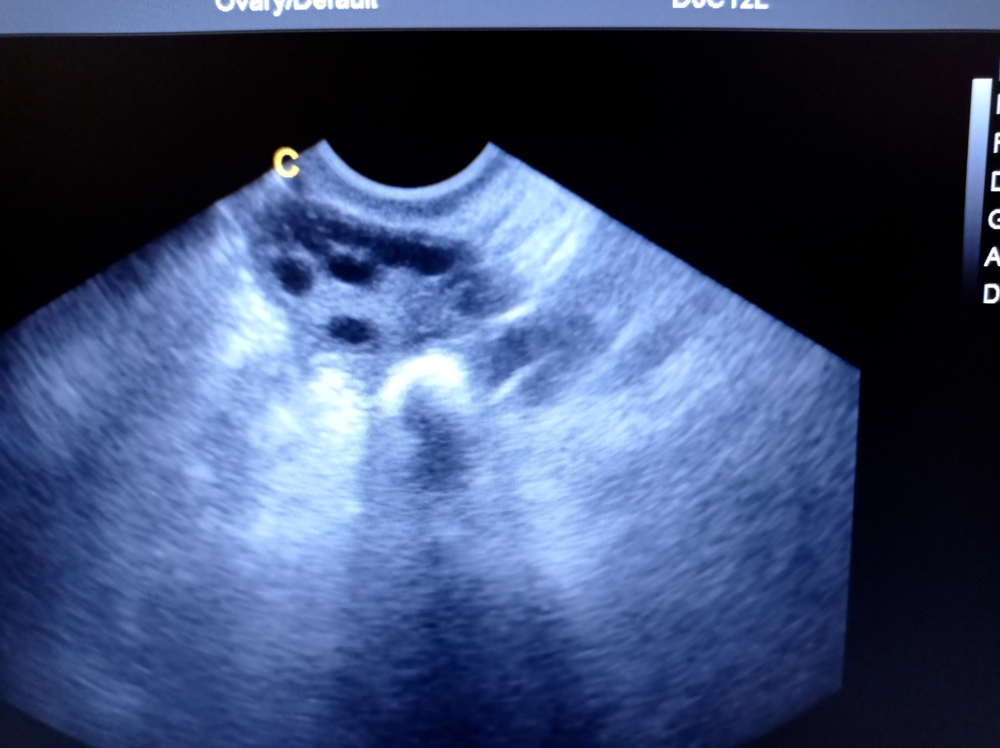

На УЗ-диагностике удается оценить размеры органов, положение, границы, отношение я рядом расположенным тканям, подвижность, наличие включений, их плотность и так далее. Состояние яичников зависит от дня цикла и возраста женщины. Изначально в норме размеры придатков у молодых девушек одинаковые. Соответственно, если увеличены яичники на УЗИ, следует провести дополнительные обследования для выяснения причины. К 35-40 годам размеры уменьшаются. В норме контуры органа бугристые, просматривается 9-10 фолликулов размером до 5 мм.

Возможны следующие отклонения в описании на УЗИ – рак яичника, кисты, поликистоз, увеличение или уменьшение размеров, внематочная беременность, желтое тело (указывает на беременность) и так далее.

Фотогалерея